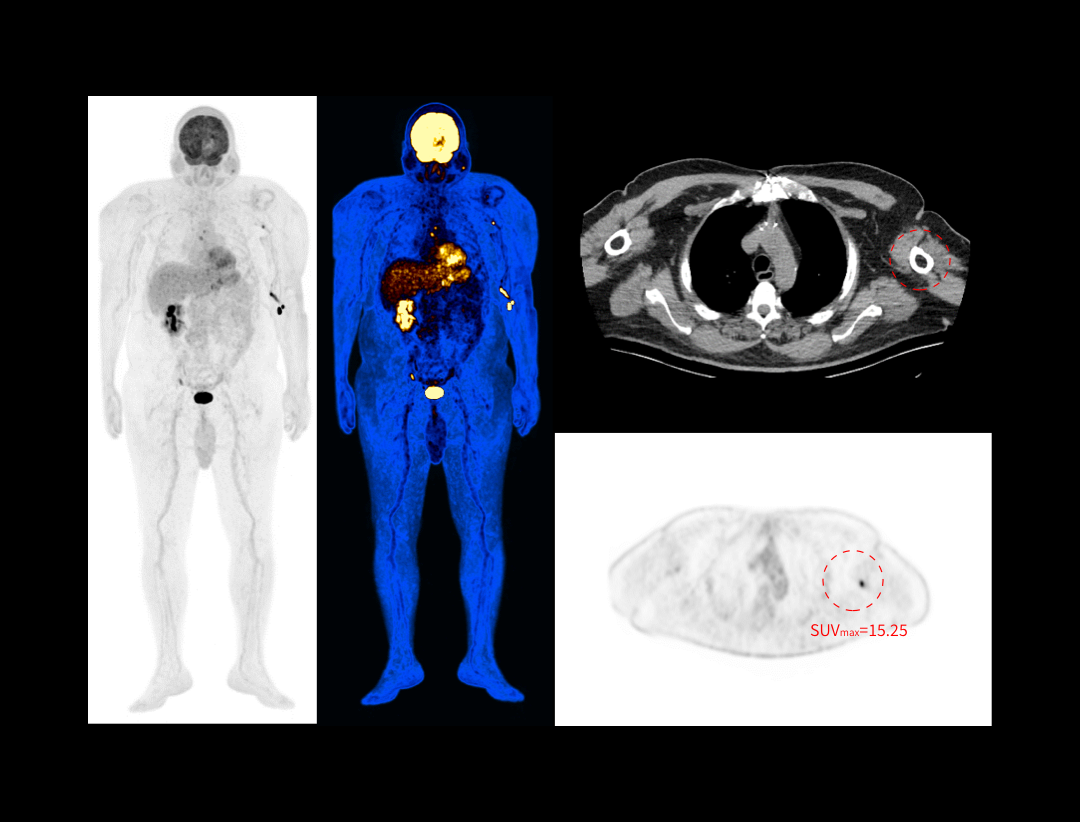

全真数字PET与160层北斗CT强强联手,将高品质的功能影像与解剖学影像精准融合,显著提升微小病灶检测精度,全面助力肿瘤、心脏和神经等重大疾病领域的精准诊疗。

2.9mm NEMA分辨率

硬件源头提升空间分辨率近40%*

*相较于空间分辨率为4mm的PET-CT系统

HYPER Iterative®4D全迭代算法

软件算法保障PET图像高清还原